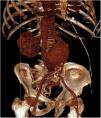

A 71-year-old man with a past medical history of arterial hypertension and a solitary kidney (right kidney) presented with sudden pain in the right iliac fossa radiating to the ipsilateral groin. On examination, a pulsatile mass was palpated in the infraumbilical region, along with a continuous murmur in the mesogastrium. He was admitted to the ICU in a dazed state with significant hemodynamic instability and tachycardia. A basal abdominal CT scan revealed a large infrarenal abdominal aortic aneurysm with signs of perianeurysmal bleeding (arrow in Fig. 1). Following contrast administration, a communication was observed between the right posterolateral wall of the aneurysm and the inferior vena cava, consistent with an aortocaval fistula (arrow in axial view Fig. 2A and coronal view B). These findings were confirmed in the 3D reconstruction performed (Fig. 3). Stent-graft implantation was decided by the heart surgical team. Eventually, the patient developed an episode of ischemic colitis and septic shock, leading to his death 7 days later.